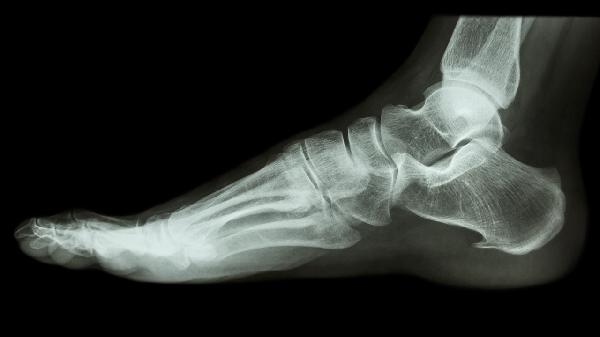

3、骨质增生

骨关节炎或椎体退变引发的骨刺压迫性疼痛,使用时可配合局部按摩。但若出现肢体麻木或持续性剧痛,可能提示神经受压,需及时就医调整治疗方案。